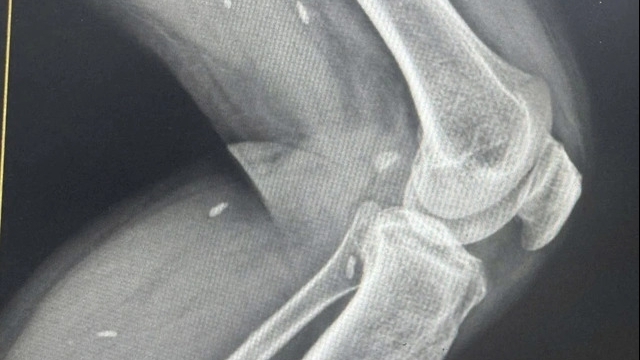

Sau đó, trẻ được đưa đến Bệnh viện Đa khoa huyện Gia Lâm, rồi chuyển tiếp đến Bệnh viện Đa khoa Xanh Pôn. Theo bác sĩ, trẻ nhập viện trong tình trạng tỉnh, hạ thân nhiệt, phản xạ sơ sinh tốt và có phản xạ bú. Trên mặt, tay chân cháu có nhiều vết trầy xước. Ban đầu chưa thấy hạn chế vận động tứ chi.

Trẻ được ủ ấm, nuôi dưỡng tĩnh mạch một phần và tiêm kháng sinh. Các xét nghiệm cận lâm sàng cho thấy hình ảnh siêu âm thóp bình thường, có rối loạn đông máu và đã được truyền plasma tươi, đồng thời theo dõi sát tình hình nhiễm khuẩn.